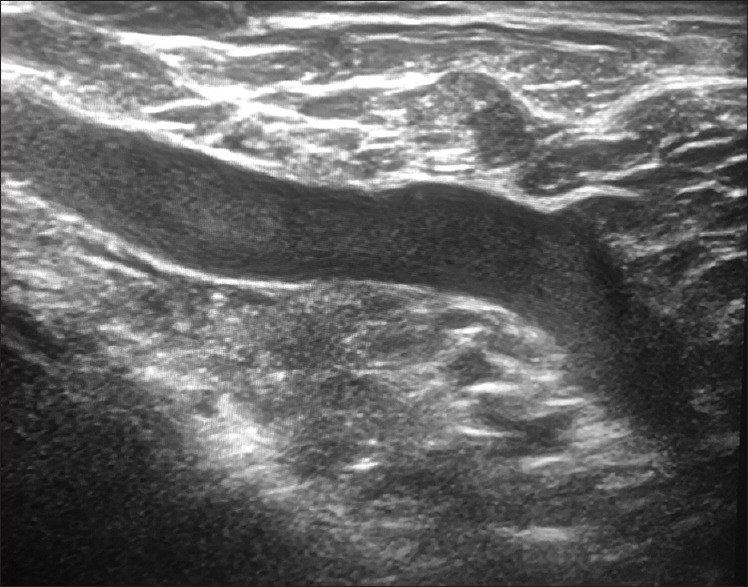

Methods: Five thousand four hundred and twenty cases were reviewed in our clinic for diagnostic breast imaging between May 2021 and May 2022. Five thousand three hundred and two of the cases were female, while 118 were male. Duplex Doppler scanning was used to assess the subclavian vein and the axillary venous structures. The same radiologist performed all examinations; in cases where suspicion was warranted, a second radiologist's opinion was acquired. The diagnosis was confirmed by consensus.

Results: In 52 cases, McCleery syndrome was identified. Between the ages of 36 and 54 years, the average age was 47 years. In four of the patients, magnetic resonance venography supported the diagnosis. In most cases, McCleery syndrome was unilateral. In only two cases was it bilateral. The incidence of McCleery syndrome was 0.95% in our study. Pain was the most often reported symptom (53.8% of 28 cases). No symptoms were reported in 26.9% of the patients.

Conclusion: During a breast ultrasound, radiologists should be aware of McCleery syndrome while assessing the axilla.